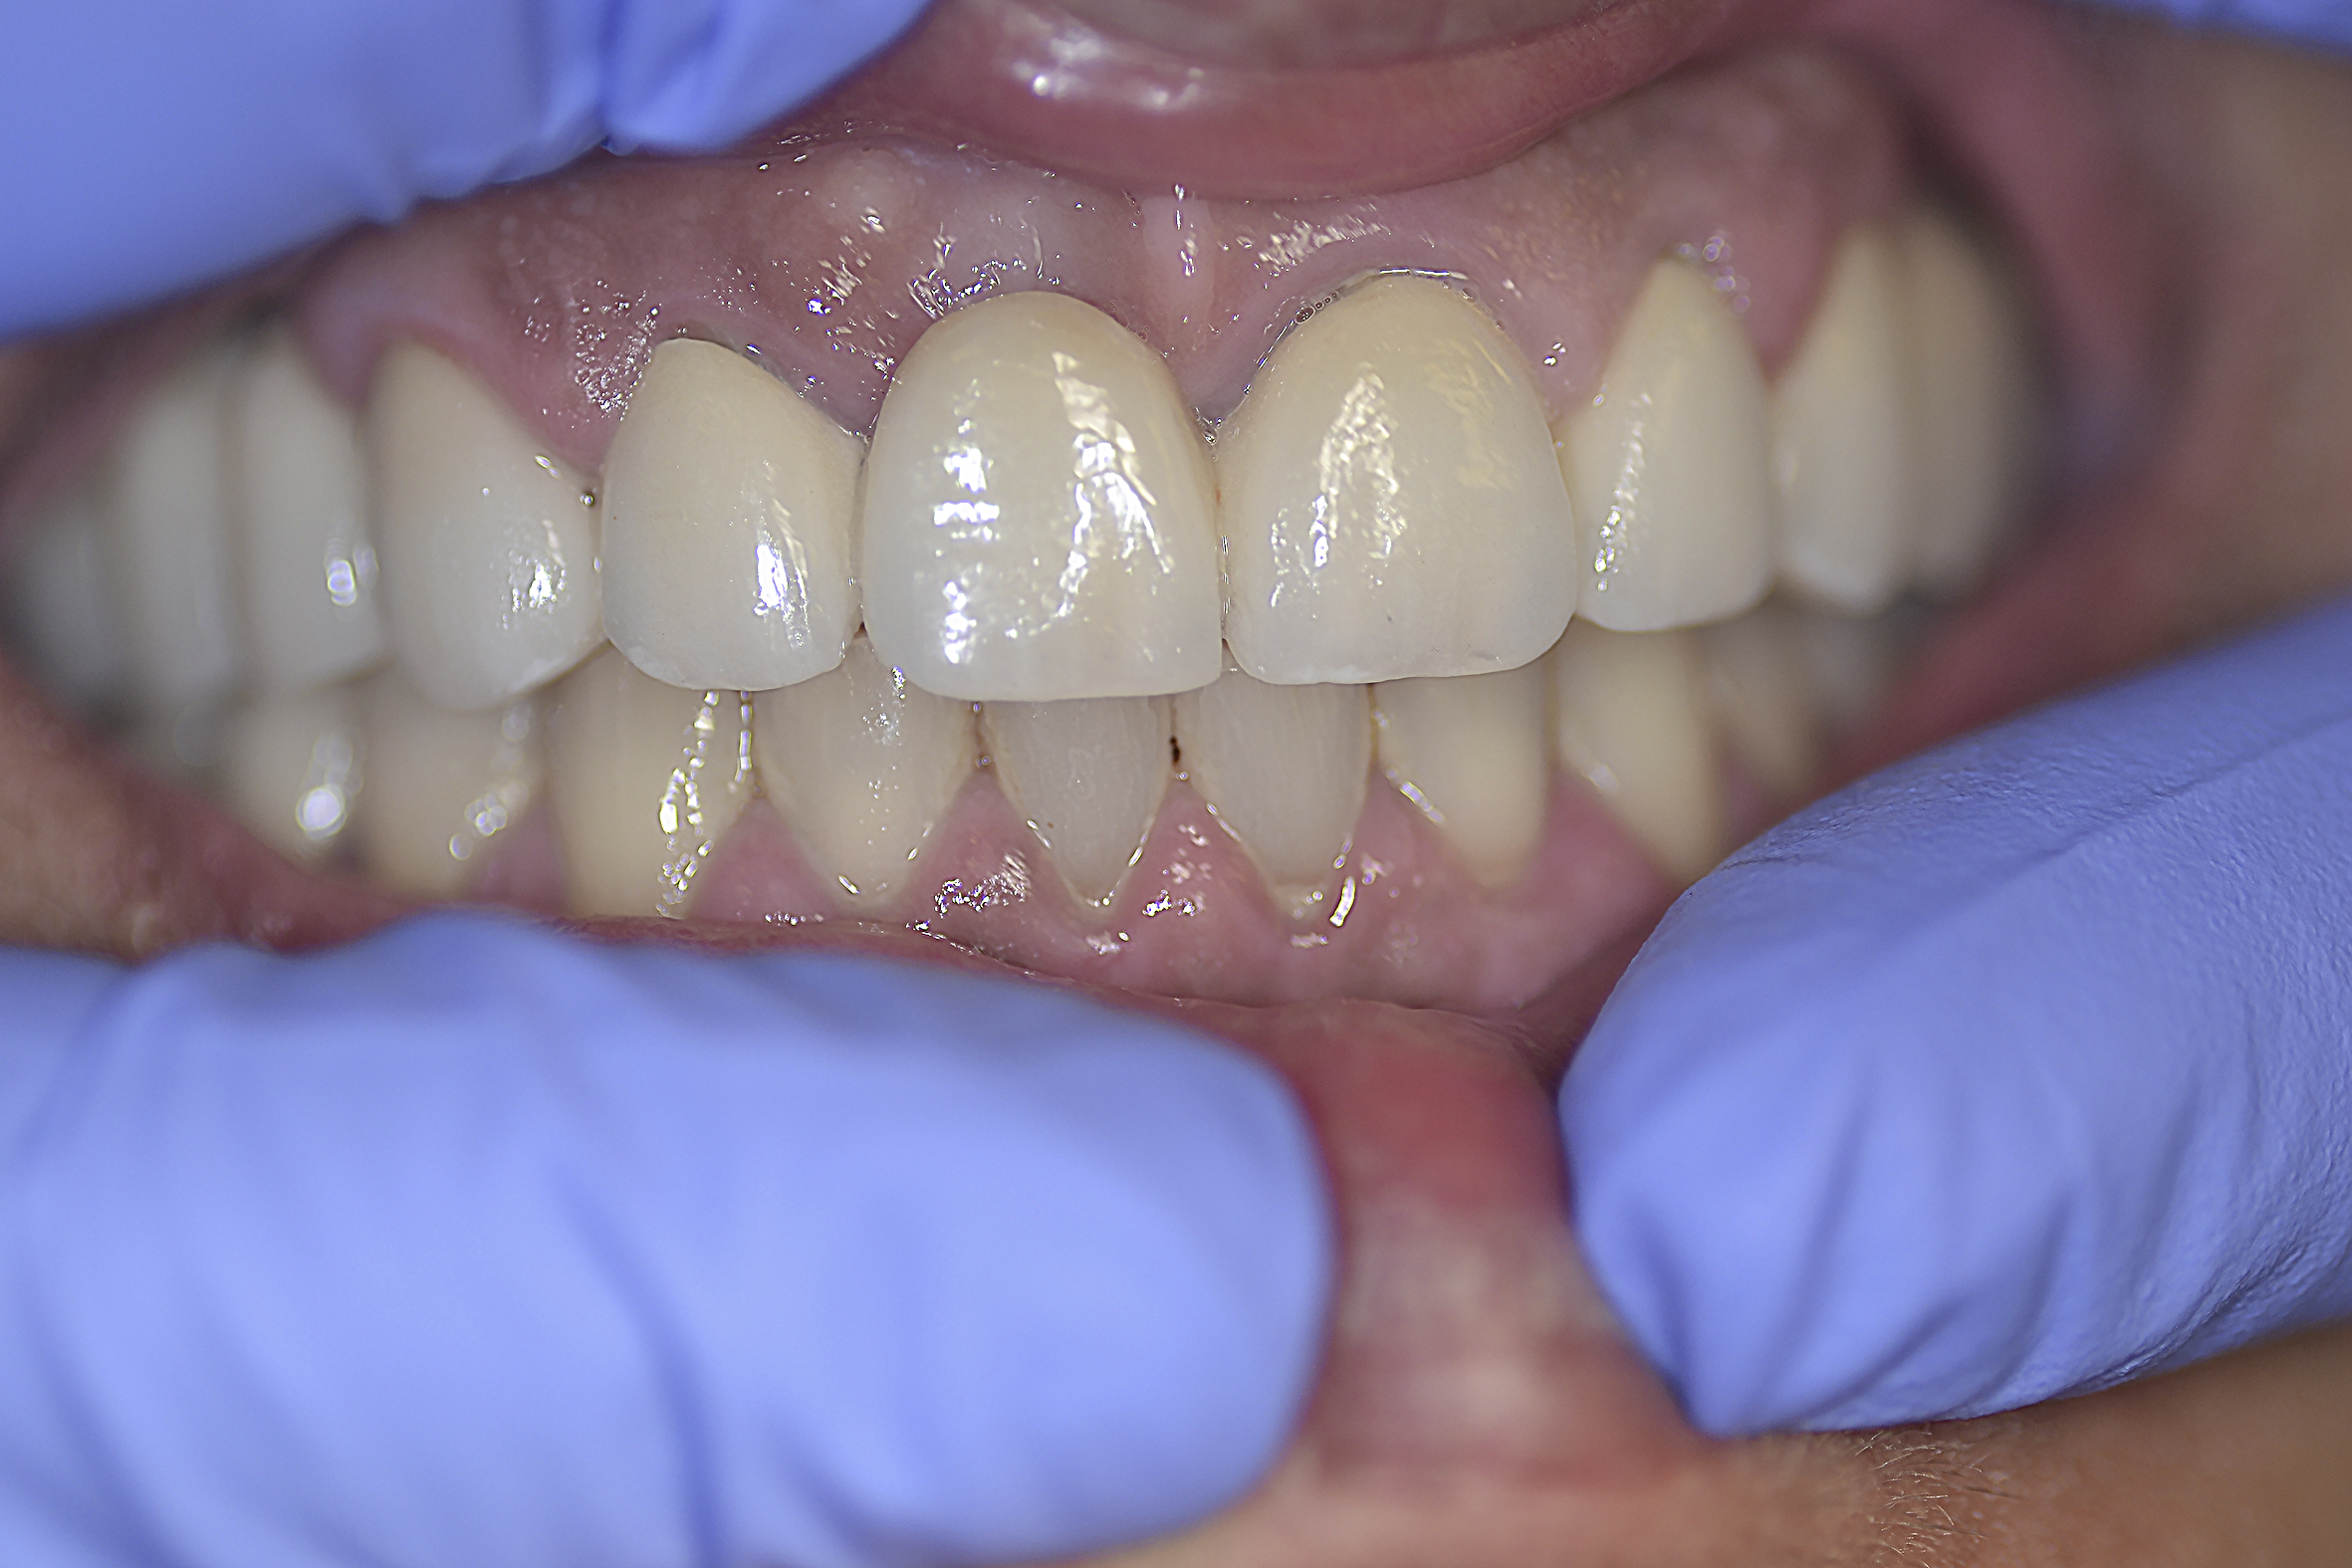

Huntington’s disease is named after George Huntington, the physician who described it as hereditary chorea in 1872. It is an incurable, adult-onset, autosomal dominant inherited disorder associated with cell loss within a specific subset of neurons in the basal ganglia and cortex.3 The most striking neuropathology in Huntington’s disease occurs within the neostriatum (Figure 2), in which gross atrophy of the caudate nucleus and putamen (Figure 3) is accompanied by selective neuronal loss and astrogliosis. Marked neuronal loss is also seen in deep layers of the cerebral cortex.4 The clinical features include a movement disorder, cognitive disorder, dementia, and behavior disorder. Patients may present with one or all disorders in varying degrees.5

Fig 2. This MRI shows the neostriatum in the brain of a child (arrows: striatum).

Figure 2